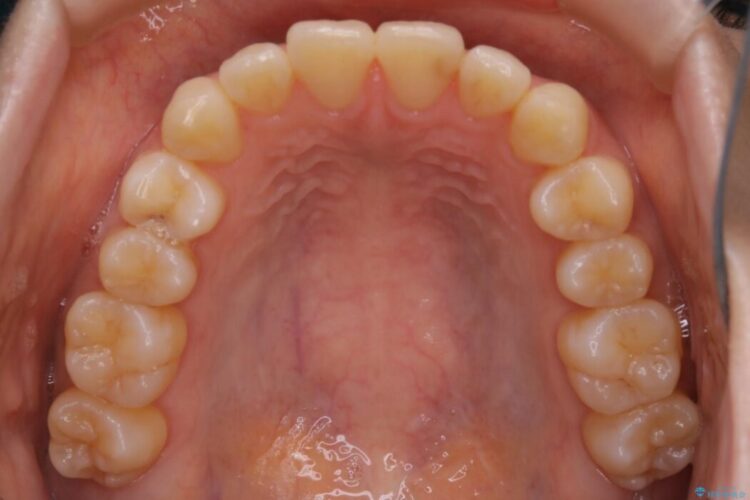

下の前歯のガタつきが気になるとご来院された患者様です。

インビザラインのライトパッケージにて、歯列拡大とディスキング(IPR)をを行いスペースをつくり非抜歯で治療を行いました。